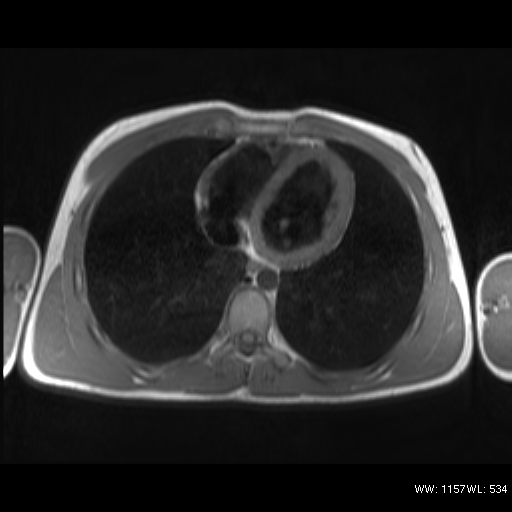

Sequenza T1 pesata dark blood nel piano assiale (TSE); valutazione morfologica del cuore e dei vasi intratoracici